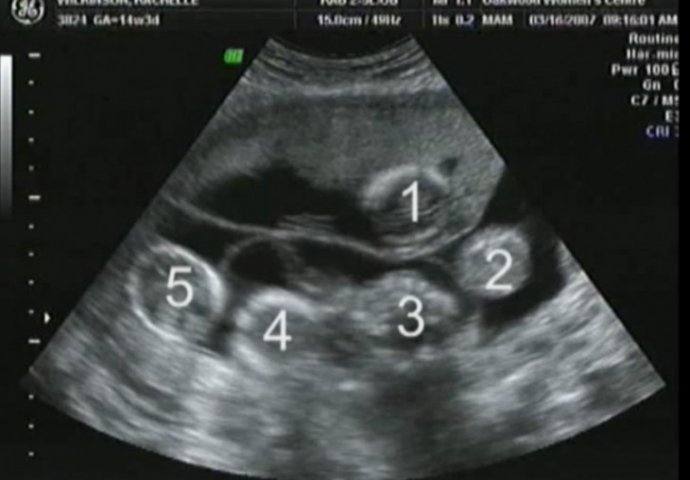

Kada su otišli na sljedeći pregled, ljekar je uočio još dva srca koja kucaju.

Najprije blizanci, a zatim treće, a onda i četvrto i peto dijete.

Rachel je nosila petorke.